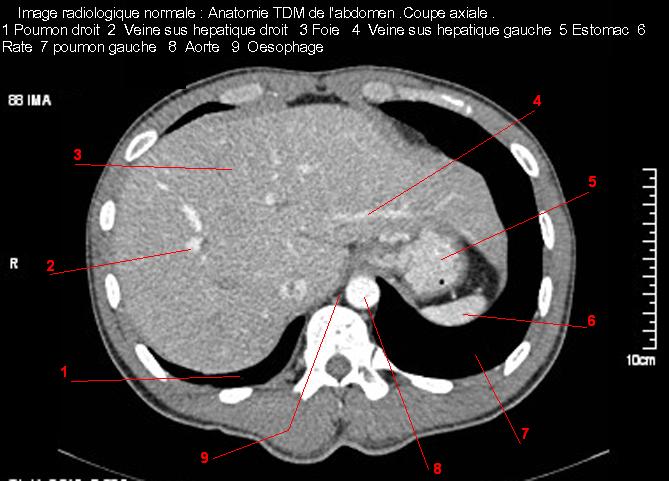

Image TDM

normale du foie :

Image TDM du foie avec

contrast intraveineuse . Coupe axiale a travers dome

du foie . Double de click pour agrandir . |

|

contrast intraveineuse . Coupe axiale a travers

bỉfurcation portale . Double de click pour agrandir . |